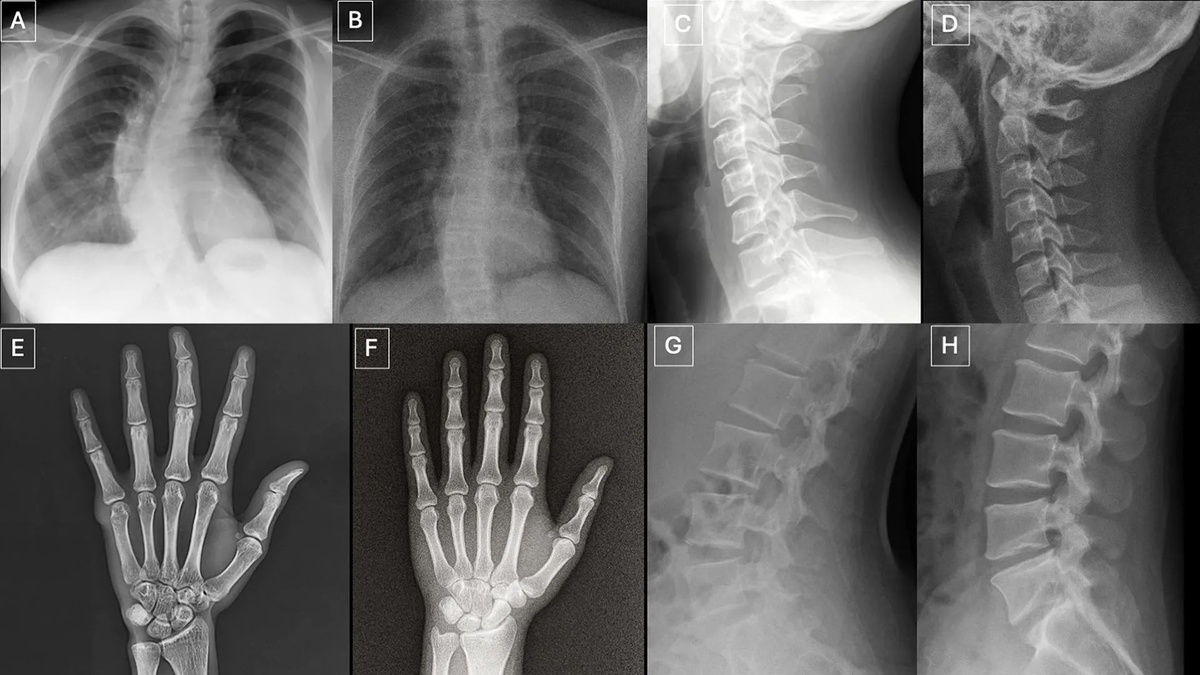

Искусственно сгенерированные рентгеновские изображения уже достигли такого уровня правдоподобия, что их распознавание вызывает затруднения не только у алгоритмов, но и у врачей-рентгенологов. К такому выводу пришли исследователи из Больницы Маунт-Синай (Mount Sinai Hospital). Авторы показали, что синтетические рентгенограммы могут быть весьма убедительными даже для специалистов, профессионально работающих с медицинскими изображениями. Работа опубликована в журнале Radiology. Авторы провели ретроспективное исследование с участием 17 рентгенологов из 12 центров в шести странах — США, Франции, Германии, Турции, Великобритании и Объединённых Арабских Эмиратах. Профессиональный стаж участников варьировал от начального уровня до 40 лет практики. Всего было проанализировано 264 рентгеновских снимка: 132 подлинных и 132 синтетических. В одном наборе использовались изображения разных анатомических областей, часть из которых была создана GPT-4o; во втором наборе оценивались рентгенограммы органо

Авторы провели ретроспективное исследование с участием 17 рентгенологов из 12 центров в шести странах — США, Франции, Германии, Турции, Великобритании и Объединённых Арабских Эмиратах. Профессиональный стаж участников варьировал от начального уровня до 40 лет практики. Всего было проанализировано 264 рентгеновских снимка: 132 подлинных и 132 синтетических. В одном наборе использовались изображения разных анатомических областей, часть из которых была создана GPT-4o; во втором наборе оценивались рентгенограммы органов грудной клетки, половина которых была сгенерирована моделью RoentGen, разработанной в Стэнфордской медицине.

По словам ведущего автора исследования, Микаэля Торджмана (Mickael Tordjman), научного сотрудника Больницы Маунт-Синай (Mount Sinai Hospital), искусственно созданные рентгенограммы нередко выглядят «слишком правильными». Для них были характерны чрезмерно гладкие костные контуры, неестественно прямой позвоночный столб, чрезмерная симметрия лёгочных полей, слишком однотипный сосудистый рисунок и подозрительно «аккуратные» линии переломов. Именно такая избыточная правильность, а не грубые дефекты, может становиться одним из косвенных признаков синтетического происхождения снимка.